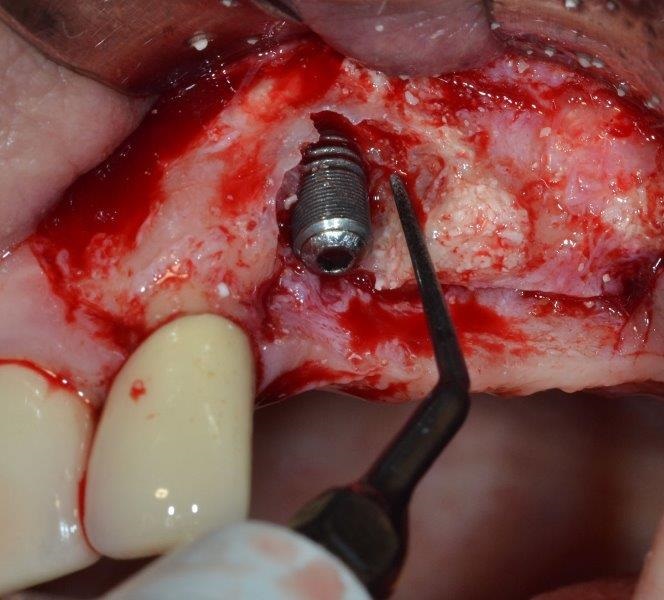

After flap elevation, a large peri-implant defect with the presence of nonintegrated biomaterial granules, perhaps remaining from a previous surgical procedure, was detected (Fig. 8). Accurate debridement of the granules embedded in reactive tissue was carried out by means of a dedicated ultrasonic tip (Fig. 9).

Horizontal bone thickness (HBT) and vertical bone defect (VBD) around the exposed part of the implant were measured at the baseline with a periodontal probe, then the cover screw was removed to decontaminate both outer and inner surface of the implant.

The ultrasonic cavitation device was placed onto the exposed part of the implant—there’s no need to create a tight seal between cavitation chamber and crestal bone—and the device was then activated (Fig. 10). A non-contact approach (without the metal tip contacting the implant) is advisable to avoid damaging the implant.